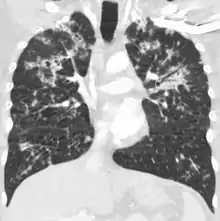

| Chest X ray showing miliary tuberculosis | |

Miliary tuberculosis is a form of tuberculosis that is characterized by a wide dissemination into the human body and by the tiny size of the lesions (1–5 mm). Its name comes from a distinctive pattern seen on a chest radiograph of many tiny spots distributed throughout the lung fields with the appearance similar to millet seeds—thus the term "miliary" tuberculosis. Miliary TB may infect any number of organs, including the lungs, liver, and spleen.[2] Miliary tuberculosis is present in about 2% of all reported cases of tuberculosis and accounts for up to 20% of all extra-pulmonary tuberculosis cases.[3]